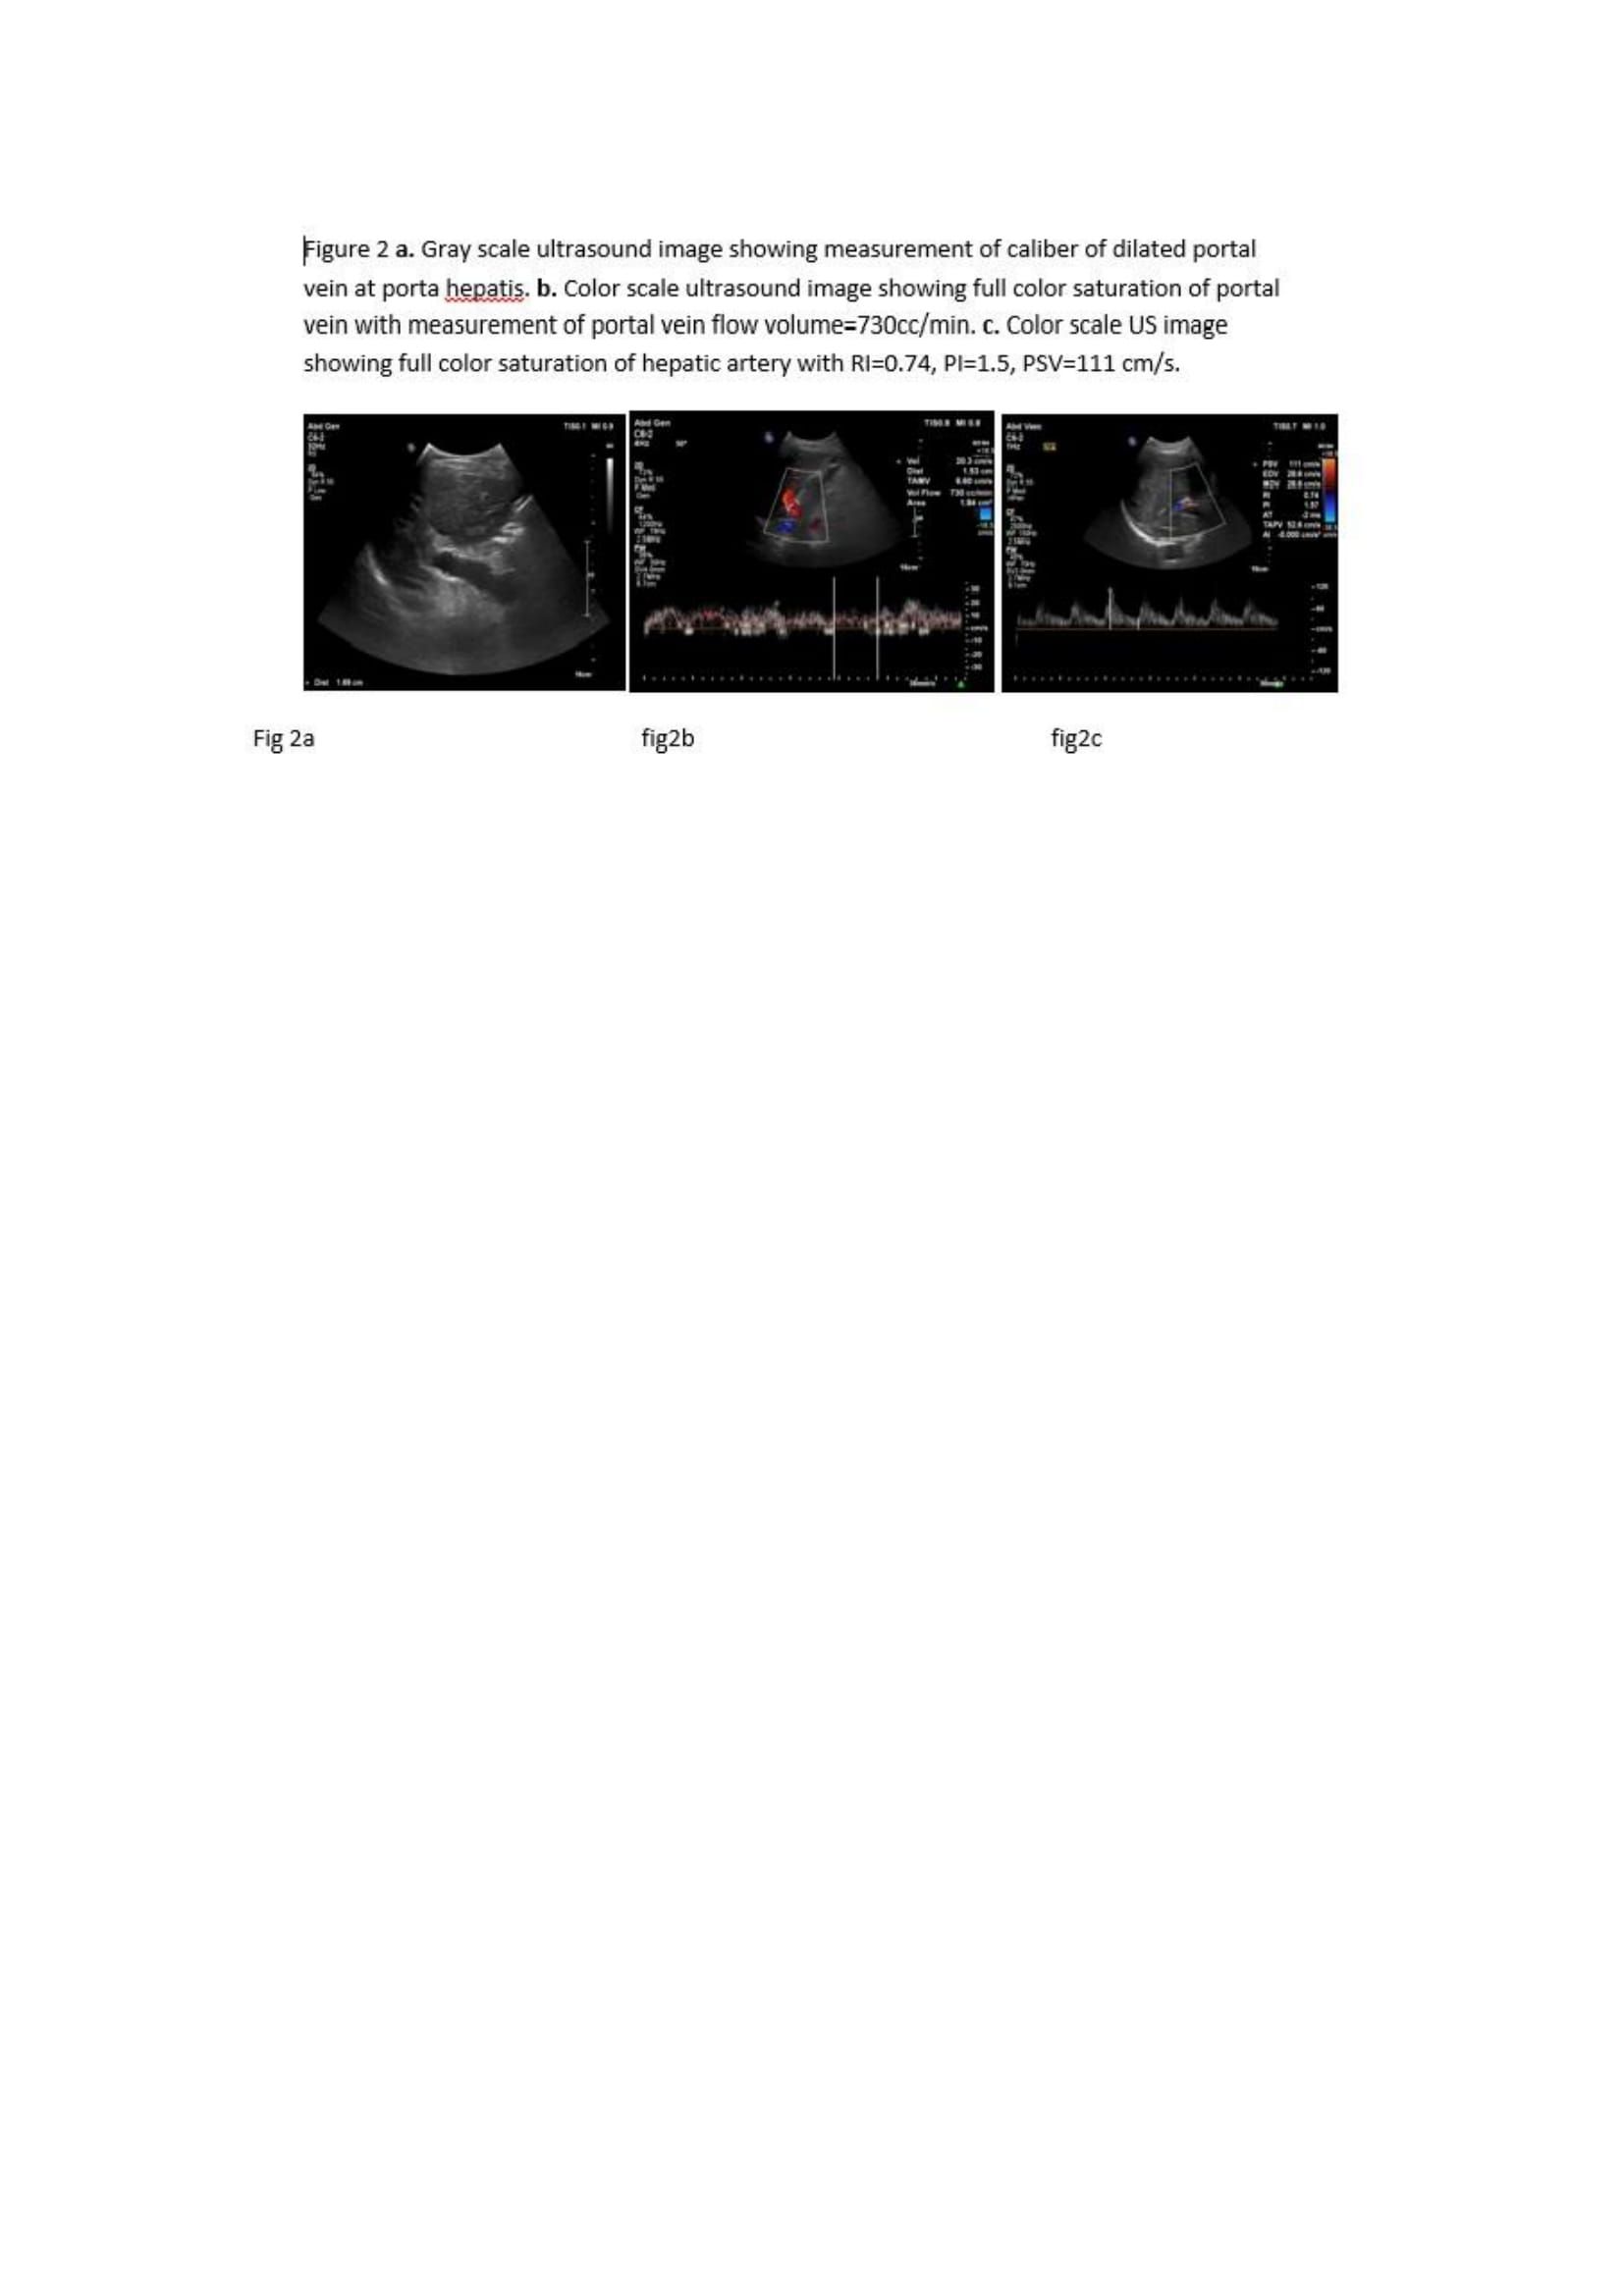

All parameters were measured by a radiology specialist. The probe was placed in the porta hepatis and at the splenic hilum. We tried to unify the method for measurement to avoid interobserver variability. Portal vein diameter (PVD) was measured in millimeters (Fig.2). The peak, smallest, and mean  flow velocity was recorded in CC/min  then portal vein flow volume (PVFV) was  automatically calculated.

Hepatic artery resistance index (HARI) was calculated using the following formula: [peak systolic velocity (V max) – end diastolic velocity/peak systolic velocity (V min)/mean velocity].

We also assess the direction of flow in portal vein, portal vein velocity (PVV) in (cm/sec).   hepatic artery pulsatility index, and splenic artery resistance index (SARI).